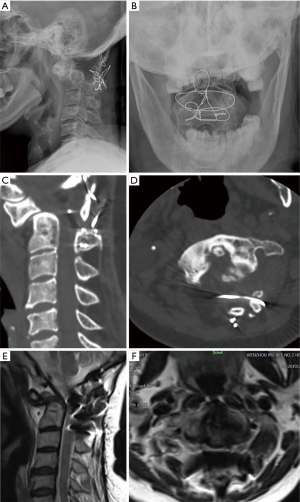

The transoral retractor was inserted with the help of tongue blade, the uvula and soft palate was pulled out of the operative field. The wound incision was made at the wall of the posterior pharynx to expose the region from C1 to C3. First, the routine discectomy was carried out in the level of C2/3, then, we used the ultrasonic scalpel to perform the bilateral osteotomy of the C2 body (Figure 2A), the region of bilateral osteotomy from the internal side of the bilateral uncovertebral joint to the 1/3 internal point of the C1 lateral mass, small inferior-internal partial of the C1 lateral mass was also removed to obtain enough space for odontoid process and the removed C2 body ventrally moved. After the bilateral osteotomy of the C2 body, the middle float C2 body was hold by Cook forceps in case of it backward move to increase the spinal cord compression, and the soft tissue connection and scars were removed by the 1–2 mm Kerrison rongeurs or nerve dissector. We also used the high-speed burr to remove the antero-inferior raised portion of C2 body and anterior raised portion of C1 arch as well as some osteophytes, to make the front of C1, C2 and C3 to be a smooth plane (Figure 2A).

Then, anterior cervical titanium alloy plate was placed at the front of C1-C3. In order to let the C2 body conform to the anterior cervical titanium alloy plate, the lower part of the C2 body was ventrally slide to the anterior plate, while the upper part of C2 body and odontoid process was ventrally rotated with the antero-inferior edge of C2 as the fulcrum (Figure 2B), therefore, we named this technique as anterior decompression through transoral “C2 slide and rotation” technique. Finally, the bilateral screws for each vertebral body were introduced to fixate the plate (Figure 2C), at this time, to avoid the C2 body backward move, the C2 body should be held by Cook forceps, and the screw trajectories were made by high-speed burr. The autogenous cancellous graft was placed at bilateral lateral atlantoaxial joint space and bilateral osteotomized gap. The posterior pharynx was closed by interrupted sutures.